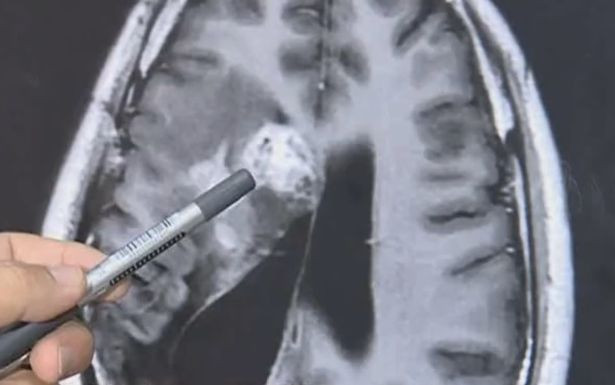

Ảnh chụp CT não của Wang.

Năm 2018, các bác sĩ phát hiện một con sán sống trong não bệnh nhân. Ở thời điểm đó, các bác sĩ chỉ định biện pháp chữa trị không phẫu thuật vì ký sinh trùng nằm ở khu vực nhạy cảm, rất khó phẫu thuật.